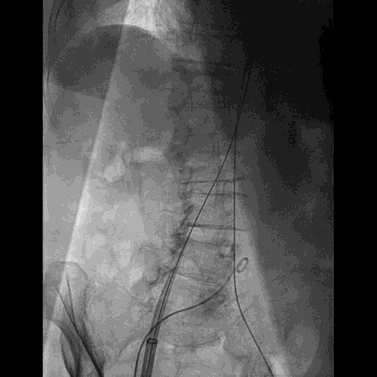

经右股静脉置入7F JR指引导管至下腔静脉,经右股动脉置入6F猪尾导管至腹主动脉,于下腔静脉及腹主动脉同时造影精确定位目标穿刺点。

穿刺系统与圈套器配合完成穿刺并建立下腔静脉至腹主动脉的通路

将0.014英寸导丝交换为超硬导丝后,置入22F大鞘达腹主动脉内。

经右侧股静脉沿超硬导丝置入22F大鞘达腹主动脉内